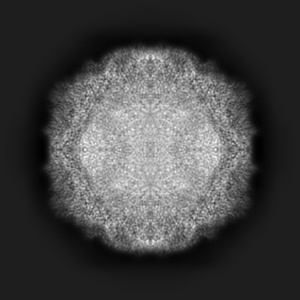

EMD-19774

Coxsackievirus A9 bound with compound 20 (CL300)

Single-particle2.26 Å